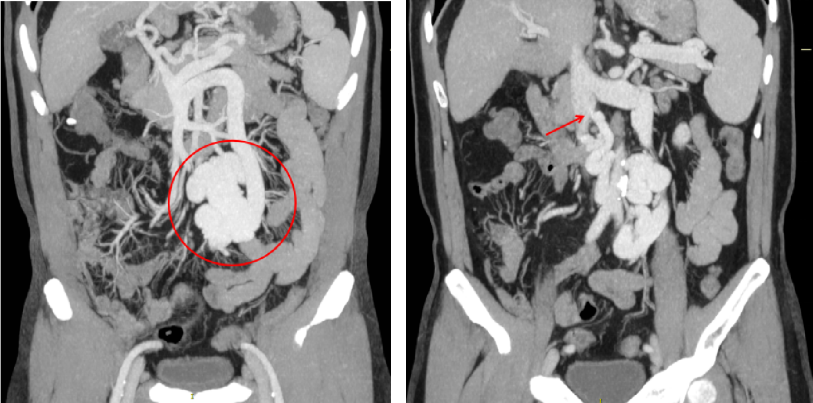

2023-08-10 多排CT全腹部直接增强:肝硬化,脾大,门静脉纤细,食管胃底静脉曲张、异常分流道(肠系膜下静脉-下腔静脉分流,引流端近下腔静脉肾静脉分叉处)

异常分流道曲张静脉较前显著萎缩

仔细评估术前CT可知,该患者的异常分流道的出口并不引流至肾上腺静脉,故难以通过常规BRTO途径栓塞,因而对于该患者团队仔细评估后决定采用TIPS联合异常分流道近端栓塞的方法。既往对于此类粗大分流道,无论是单纯使用可控弹簧圈或是弹簧圈联合组织胶水都存在栓塞效率或是安全性的不足,该患者使用血管塞封堵减缓血流后,在血管塞细密的网孔阻隔下能够有效防止补充栓塞的组织胶逃逸,进而获得良好的栓塞效果及效率。

术后患者的肝脏血管超声提示患者原本的离肝血流已逆转为向肝血流,1月后的CT复查显示门静脉较术前的纤细状态已得到明显恢复,间接证实TIPS分流并未进一步降低患者的肝脏灌注,其随访至今也未在发生肝性脑病。对于自发性门体分流所致的反复肝性脑病患者,相信TIPS+异常分流道近端栓塞是值得进一步探索研究的治疗方法。需临床进一步验证。